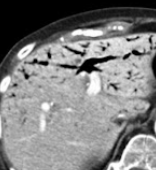

Repeat abdominal CT scan demonstrating complete resorption and disappearance of air from the stomach and the portal venous system (Courtesy Dr. V. Penopoulos)